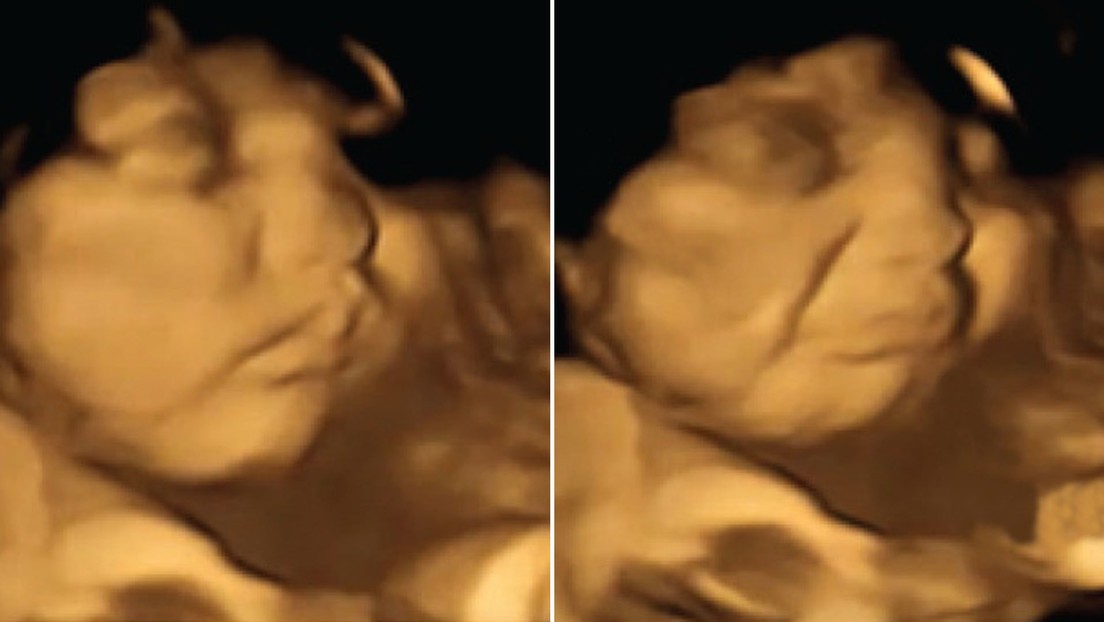

Investigadores de la Universidad de Durham, Reino Unido, dirigieron un estudio que mostró la primera evidencia directa en imágenes de que los bebés reaccionan con expresiones faciales de manera diferente a varios olores y sabores mientras están en el útero.

Los científicos tomaron ecografías 4D (imagen del feto en tres dimensiones en tiempo real) de 100 mujeres de 18 a 40 años, con un periodo de gestación de entre 32 y 36 semanas.

Los fetos expuestos al sabor de zanahoria mostraron más respuestas de "cara de risa", mientras que los expuestos al sabor de col rizada mostraron más respuestas de "cara de llanto". La exposición a solo una pequeña cantidad de estos vegetales fue suficiente para estimular una reacción de disfrute o desagrado hacia estos alimentos.